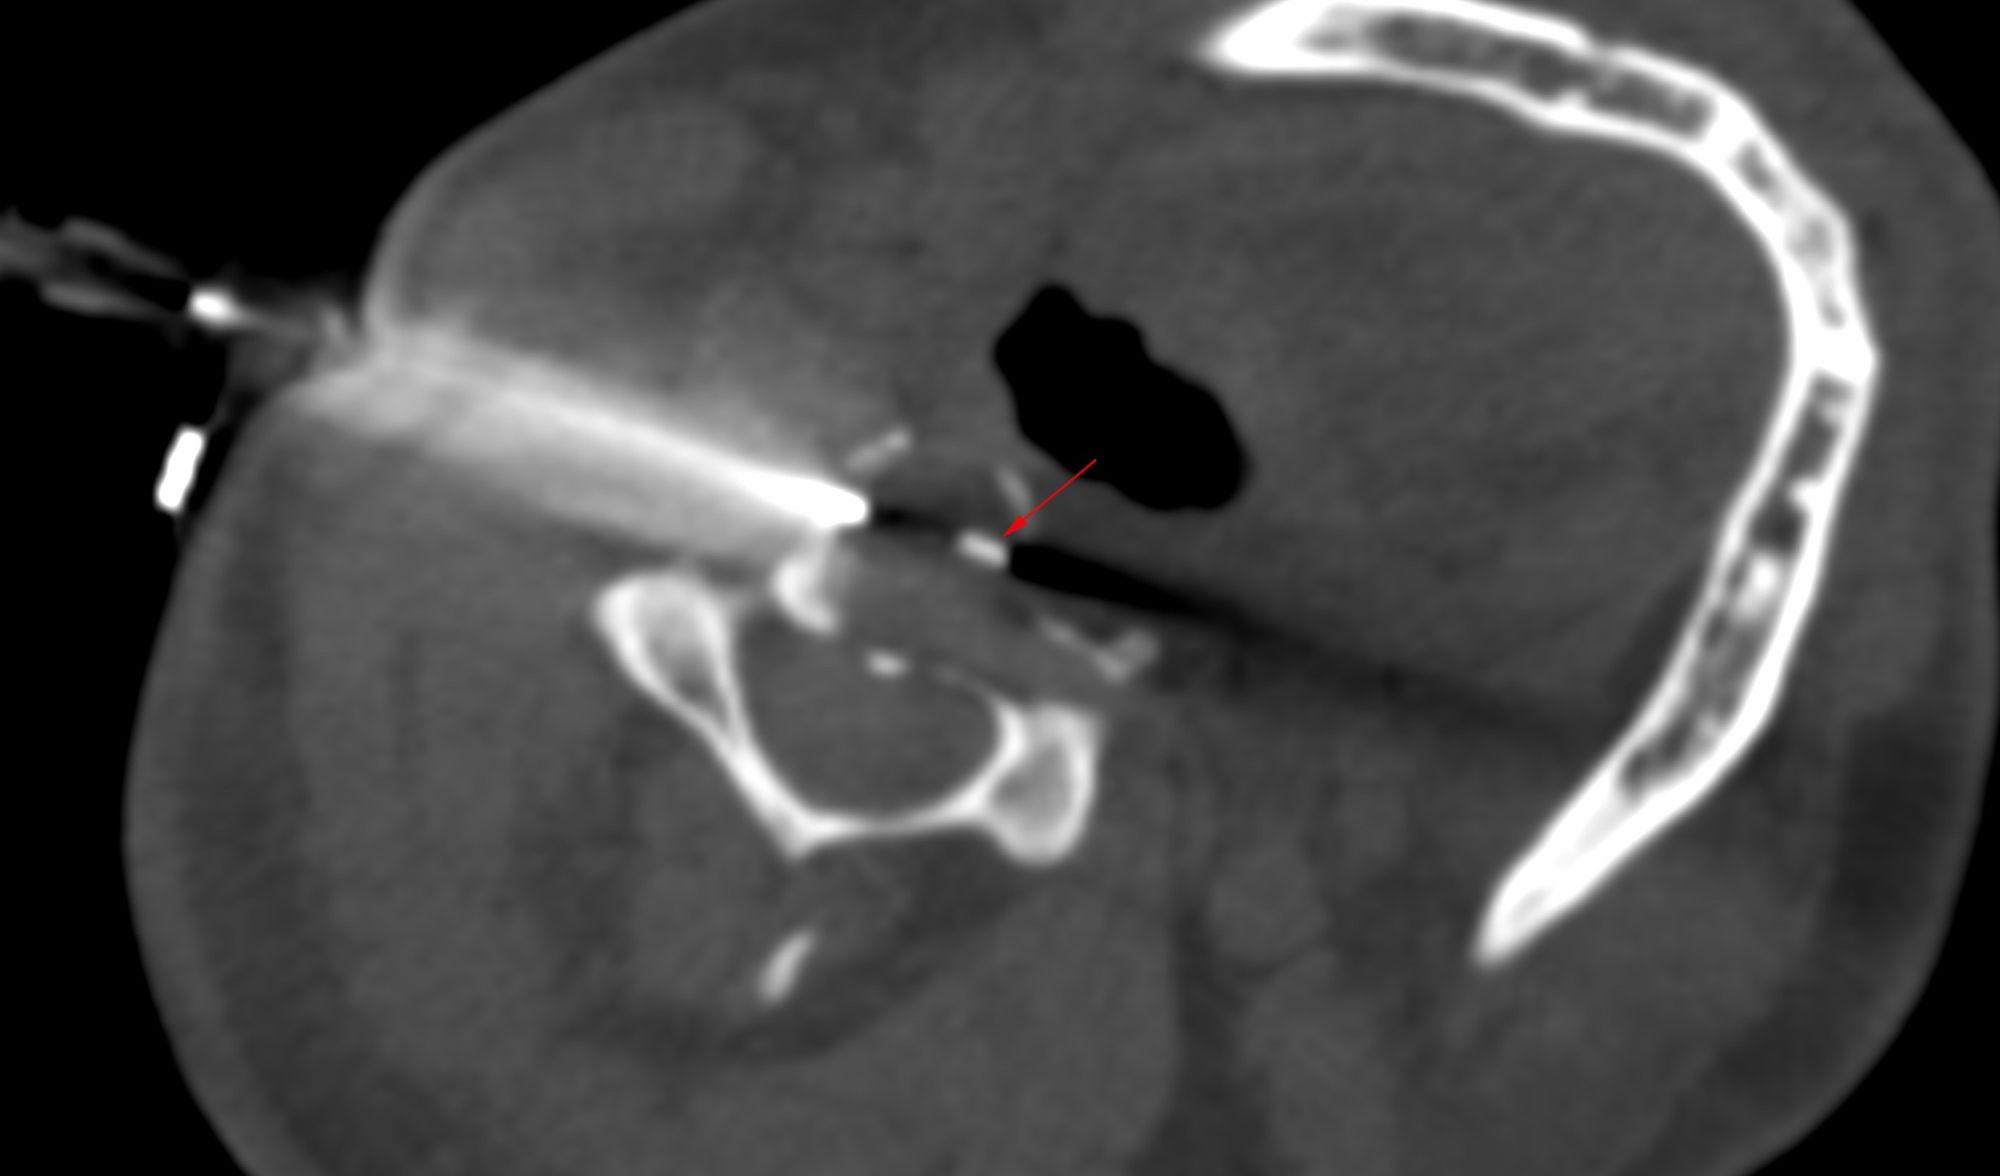

Case 33: Retrocrural Mass Biopsy - The Difference Between "It Can't Be Done" and "I Can't Do It"

Bhavin Jankharia - 15 May 2021